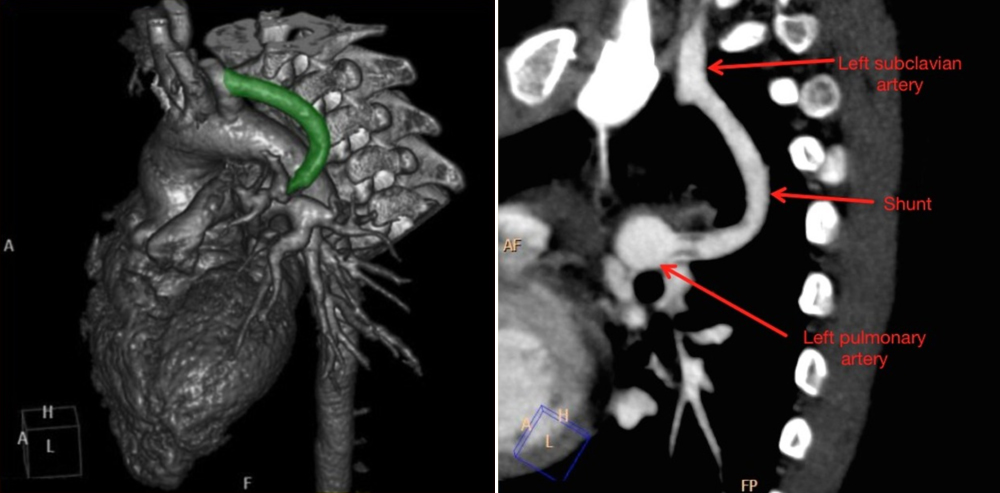

영화에서 토마스는 블래락의 어깨뒤에서 수술을 잘 도와서 blue baby가 pink baby로 변하게 되는 모습을 극적으로 보여주는데, 마치 심도자실에서 절대 뚫릴 것 같지않던 험한 관상동맥병이 시술팀의 조언과 도움으로 와이어가 통과되고 재관류가 되어 환자가 살아나는 통쾌함을 느끼게 해준다. 이때 시행되었던 TOF 수술법은 좌쇄골하동맥을 폐동맥에 연결하여 폐순환을 돕도록 하는 방식으로 현재 Blalock-Taussig (BT) Shunt 라는 수술법으로 알려져 있고, 수술의 성공에 큰 역할을 한 토마스의 공을 사서 Blalock–Thomas-Taussig shunt [그림3]라고도 부른다2.

[그림 3] Blalock–Thomas-Taussig shunt